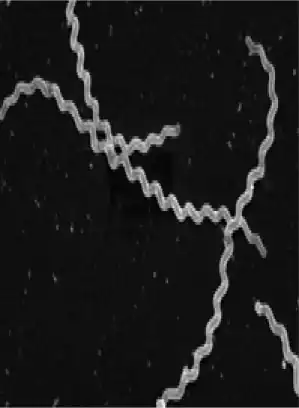

| Scanning electron micrograph of Leptospira interrogans. | |

Leptospira interrogans is a species of obligate aerobic spirochaete bacteria shaped like a corkscrew with hooked and spiral ends.[1] L. interrogans is mainly found in warmer tropical regions. The bacteria can live for weeks to months in the ground or water.[2] Leptospira is one of the genera of the spirochaete phylum that causes severe mammalian infections.[3] This species is pathogenic to some wild and domestic animals, including pet dogs. It can also spread to humans through abrasions on the skin, where infection can cause flu-like symptoms with kidney and liver damage.[2] Human infections are commonly spread by contact with contaminated water or soil, often through the urine of both wild and domestic animals.[2] Some individuals are more susceptible to serious infection, including farmers and veterinarians who work with animals.[4]

L. interrogans cells are gram-negative, tightly coiled, motile spirochetes, with two periplasmic flagella.[1] One flagellum is inserted at each end of the bacterium. The cells are thin, about 0.15 µm, and long, between 6-20 µm, with a corkscrew shaped body with spiral or hooked ends.[1] The hooked ends often resemble a question mark, and this is where the name ‘interrogans’ comes from.[11] The periplasmic flagella are crucial to the bacteria's ability to move and survive in specific host cells. The leptospires reveal two unique forms of movement, translational and non translational.[12]